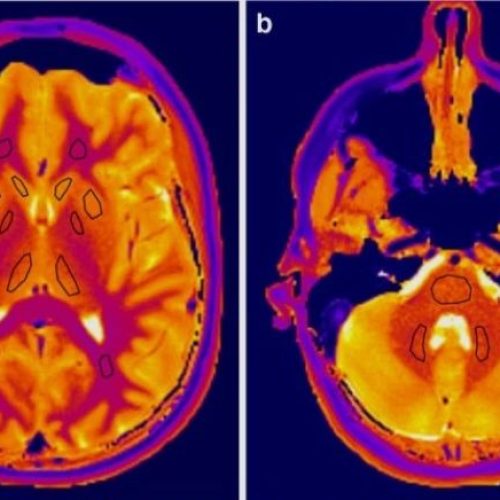

Dr. Guanyuguang, a renowned expert in functional neurosurgery, specializes in treating complex neurological conditions such as epilepsy, Parkinson’s disease, and movement disorders. With over 6,000 successful epilepsy surgeries and groundbreaking...

Dr. Guanyuguang: Leading Expert in Functional N...

Professor Guoming Luan: Leading Expert in Funct...

Professor Luan Guoming is a distinguished neurosurgeon specializing in functional neurosurgery. With over 40 years of experience, he has made significant contributions to the treatment of epilepsy, Parkinson's disease, and...